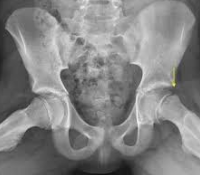

そのほか人用には、大腿骨頸の骨折と転子貫通骨折に対して大転子から刺入するため、先端に刃をつけ、また130°にまげた有刃プレート(130°blade plate)、大腿骨上顆骨折や転子貫通骨折に使用する顆用プレート(condylar plate)、真直ぐな細い骨に使用する半管状プレートなどがあります。